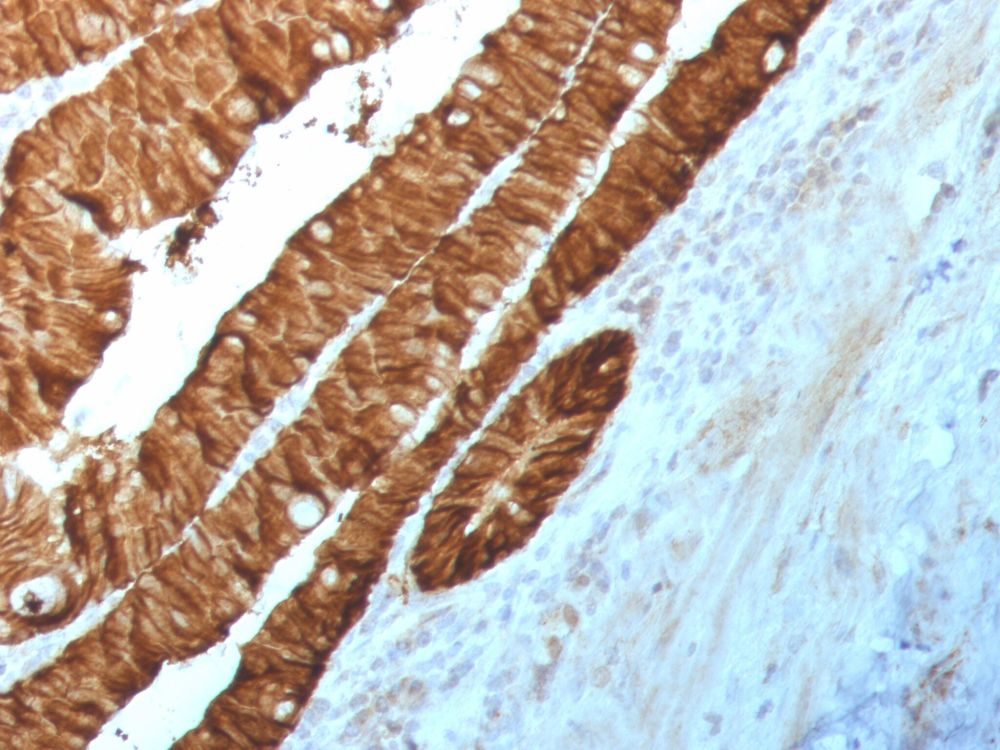

Elabscience® offers various high-quality conjugated/unconjugated secondary antibodies which can be applied in fluorescence detection of the primary antibody, and they are suitable for conventional applications such as IF, IHC, WB and Flow cytometry, etc.